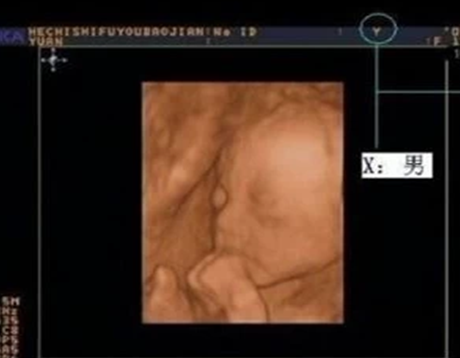

怎么通过四维彩超的数据判断性别?几个月做最佳?

孕期知识

自古以来人们就对宝宝的性别充满了好奇,不论是重男轻女的时代还是男女平等的现代都拥有一样的想法,但随着国家发展进步为了防止恶性的流产情况发生,禁止各个家庭在胎儿出生前就鉴定性别,但也有少数特殊情况可以进...

怎么通过b超判断性别?会有失误吗?

对于男性女性来说组建一个家庭就已经是非常幸福的一件事情,除此之外拥有可爱的宝宝可以说是喜上加喜,但由此也伴随出烦恼,对于宝宝的性别是男孩还是女孩也泛起了忧愁,我们往往充满了好奇心,都想要在不可能的情况...